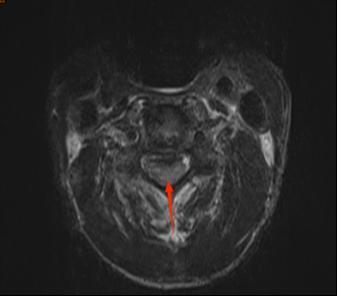

近日,我院收治一名高龄男性患者,诊断为“颈4椎骨折、颈脊髓损伤伴完全四肢瘫”,合并肺部感染与深静脉血栓,胸骨柄平面以下感觉活动消失,生活完全依赖,且面临呼吸衰竭、压损等高危风险,护理挑战极大。

1.2  患者术前影像